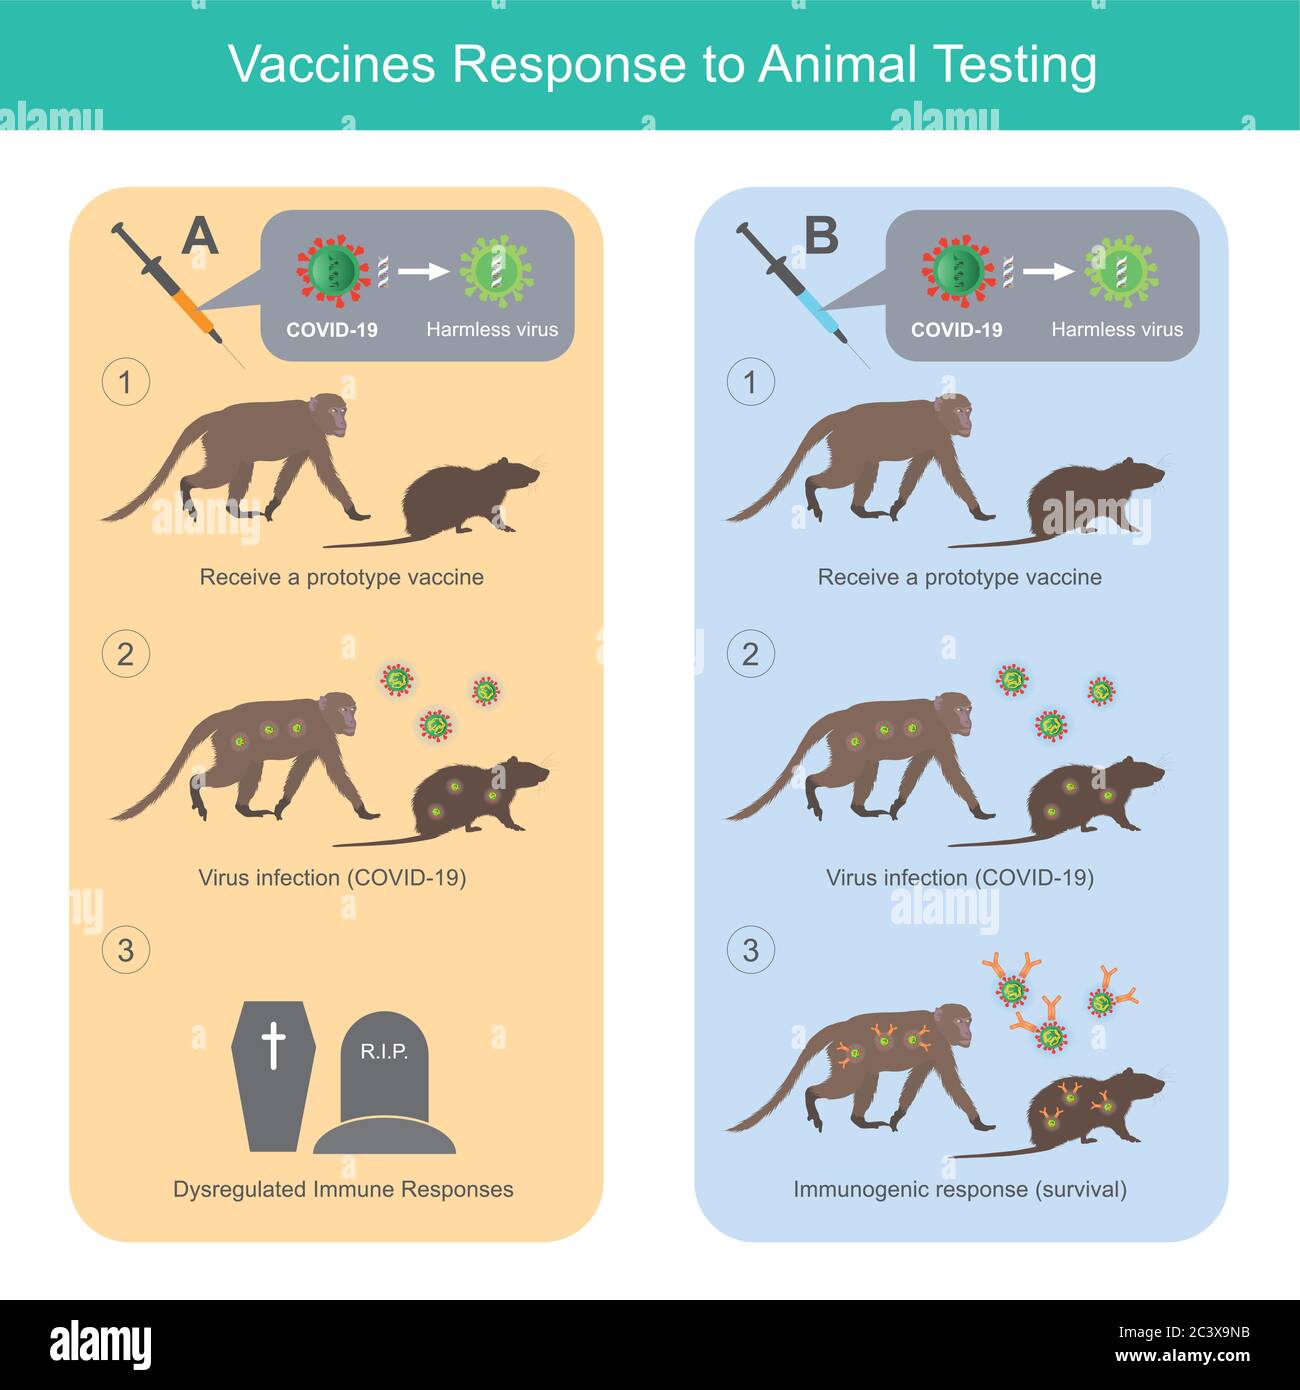

Risposta dei vaccini ai test sugli animali. Illustrazione per uso medico per confrontare i vaccini di tipo 2, che ha effetti diversi sulla sperimentazione animale (scimmia e. Illustrazione Vettorialehttps://www.alamy.it/image-license-details/?v=1https://www.alamy.it/risposta-dei-vaccini-ai-test-sugli-animali-illustrazione-per-uso-medico-per-confrontare-i-vaccini-di-tipo-2-che-ha-effetti-diversi-sulla-sperimentazione-animale-scimmia-e-image363840103.html

Risposta dei vaccini ai test sugli animali. Illustrazione per uso medico per confrontare i vaccini di tipo 2, che ha effetti diversi sulla sperimentazione animale (scimmia e. Illustrazione Vettorialehttps://www.alamy.it/image-license-details/?v=1https://www.alamy.it/risposta-dei-vaccini-ai-test-sugli-animali-illustrazione-per-uso-medico-per-confrontare-i-vaccini-di-tipo-2-che-ha-effetti-diversi-sulla-sperimentazione-animale-scimmia-e-image363840103.htmlRF2C3X9NB–Risposta dei vaccini ai test sugli animali. Illustrazione per uso medico per confrontare i vaccini di tipo 2, che ha effetti diversi sulla sperimentazione animale (scimmia e.